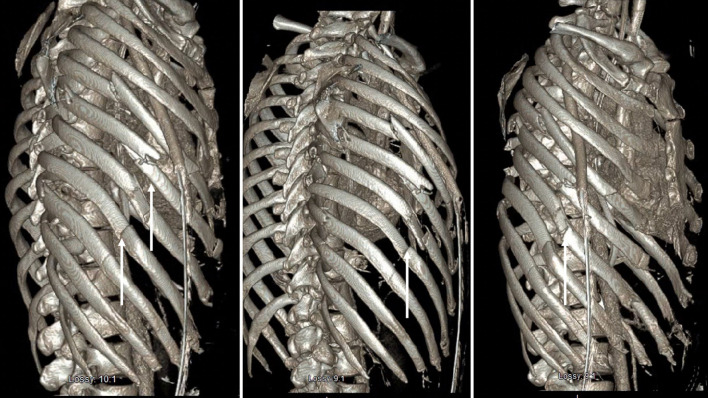

对于多发性肋骨骨折或胸部外翻的患者来说,肋骨固定是一种值得推荐的干预措施,可改善呼吸急促、显著减轻疼痛并缩短住院时间。在此,我们报告了一名胸内肋骨固定术后出现肺水肿患者的独特且极其罕见的发现。一名有酗酒史的 32 岁男性在一次车祸后被送往急诊科创伤室。计算机断层扫描(CT)显示患者右侧血气胸,第四至第九根肋骨骨折并移位。随后使用钛合金 RibFix 固定桥对右侧第五和第六根肋骨进行了固定,并沿肋骨后表面植入胸腔内。术后第 11 天,患者出现肺水肿,在 CT 引导下将引流导管置入积水处。患者接受了为期 3 天的组织浆肌酶原激活剂(tPA)和 DNase 治疗。术后第 15 天,复查 CT 扫描显示,患者的肺水肿明显好转,有证据表明脓肿已经消退。总共 7 天后,患者停用了抗生素,并于术后第 20 天出院。本病例报告为胸腔内肋骨固定术并发症的处理提供了信息。

Rib plating is a recommended intervention for patients with multiple rib fractures or flail chest to improve shortness of breath, significantly reduce pain, and shorten the length of hospital stay. Here, we report a unique and extremely rare finding in a patient with empyema following intrathoracic rib fixation. A 32-year-old male with a history of alcohol use disorder presented to the emergency department trauma bay after a motor vehicle accident. Computed tomography (CT) showed right hemopneumothorax and fourth to ninth rib fractures with displacement. The right fifth and sixth ribs were then plated using a titanium RibFix bridge, implanted intrathoracically along the posterior surface of the ribs. On postoperative day 11, the patient developed an empyema and a CT-guided drainage catheter was placed into the collection. The patient was given a 3-day course of tissue plasminogen activator (tPA) and DNase for the treatment of his empyema. On postoperative day 15, a repeat CT scan demonstrated significant improvement in the empyema with evidence of abscess resolution. Antibiotics were discontinued after a total of 7 days and the patient was discharged on postoperative day 20. This case report contributes information to the management of complications in intrathoracic rib fixation.